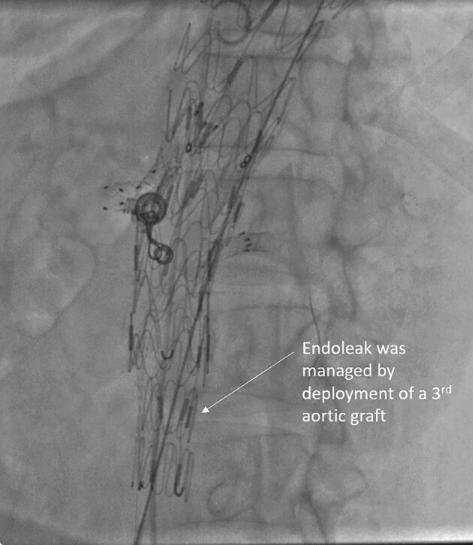

每六个月对病人进行一次CT主动脉造影随访。在两次为期两年的随访中,CT血管造影显示腹主动脉囊状动脉瘤因IB型内漏而增大(图3)。内漏是由于肾下主动脉疾病的远端进展。通过在远端部署28×28×100 TAA支架移植物对其进行管理(图4)。通过部署6×27mm支架来加固左肾支架。术后主动脉造影证实动脉瘤被排除,SMA和左肾动脉血流通畅。后续CT显示动脉瘤段完全排除(图5)。患者每天服用75毫克阿司匹林、抗高血压药、口服泼尼松龙和托法替尼。

图4、内漏修复。通过在远端放置第三个主动脉支架移植物来治疗IB型内漏